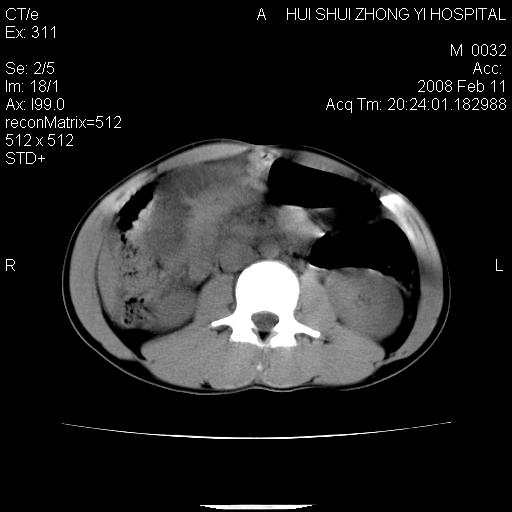

8年前曾在贵洲省人民医院b超诊断为肝内胆管结石。现腹痛剧烈,现发烧、头痛、恶心呕吐县医院b超示胆囊肿大大小159*46mm,囊内见6*5mm强回声光团,胆各总管内径56mm。提示:胆囊结石、急性胆囊炎、胆总管重度扩张。

胆囊结石.急性胆囊炎.重度胆管扩张.右侧胸腔少量积液,建议ct增强

考虑先天性胆管囊肿;胆囊增大并结石。右侧胸腔少量积液,建议ct增强。

caroli囊肿并囊内结石。胆囊增大并胆结石。典型!

先天性胆管囊肿,胆囊结石、胆囊增大,右侧少量胸腔积液。